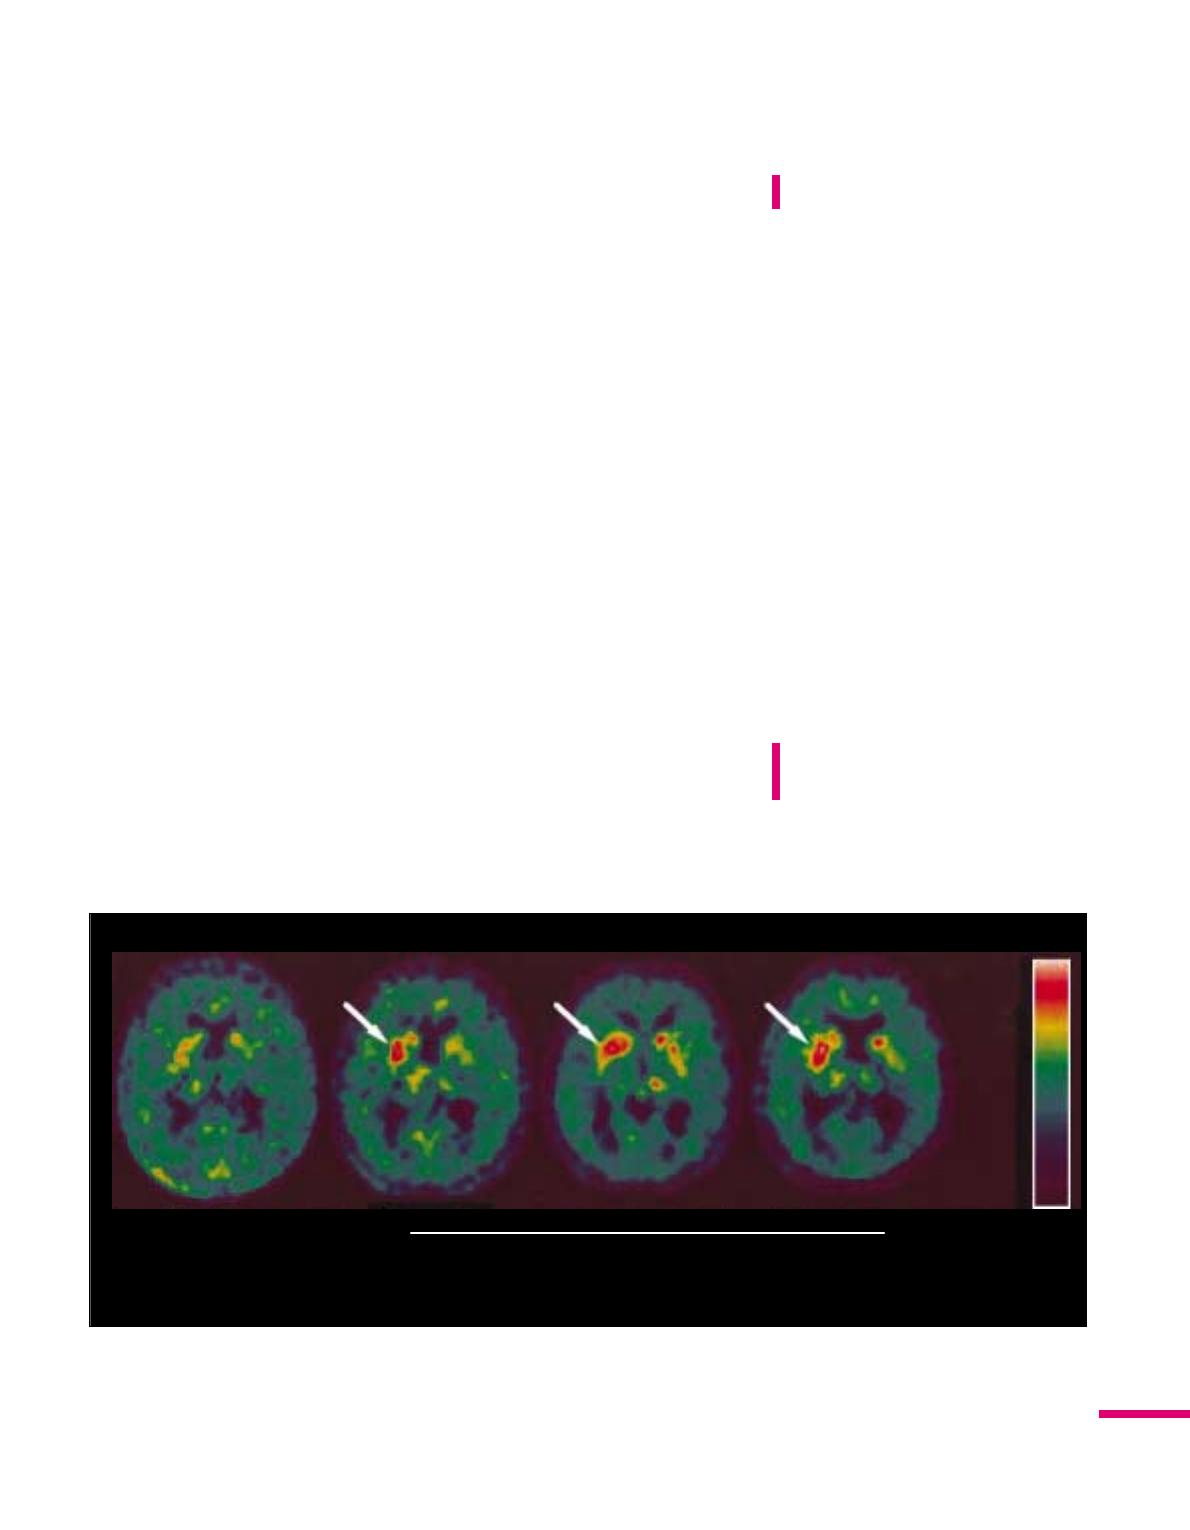

D G

Avant 3 mois 6 mois 12 mois 0

2

Après la greffe

[18F]- Fluorodopa

Figure 2. Captage striatal de la 18F-Dopa au cours du temps chez un malade parkinsonien greffé.Ce patient a été

greffé dans le putamen droit (à gauche sur les images). On constate 3, 6 et 12 mois après la greffe une augmen-

tation du captage du traceur dans cette région (flèche) qui correspond à la survie et à la synthèse de dopamine par

les neurones fœtaux implantés. D : droite; G : gauche.